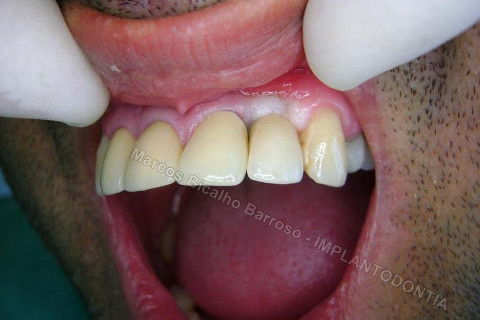

Este caso tem o objetivo de demonstração da técnica que normalmente sigo ; em casos onde ocorre fratura da raiz e consequentemente abscessos, com ou sem formação de fístula. Neste caso fiz a exodontia com preenchimento do alvéolo com biomaterial (osso bovino liofilizado + coágulo do paciente). Após 90 dias, mais ou menos, instalei o implante. Esperei mais 4 meses e realizei ontem (12/11/2010) a instalação do cicatrizador com o cuidado de preservar tecido mole, sem remoção de material, apenas afastando gengiva e "enrolando" a sobra de mucosa em direção a face vestibular, para promover conservação de papila futuramente. Se ocorrer excesso de papila, sem problema, remove-se um pouco, mas a intenção é não deixar faltar, o que resultaria em indicação para enxertos gengivais.